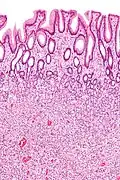

Hyperplastic polyp Colorectal (unless otherwise specified) Serrated unbranched crypts if polyps are more than 100

Hyperplastic polyp of the stomach Stomach Elongated, tortuous, and cystic foveolae separated by edematous and inflamed stroma.[14]

Micrograph of a Peutz–Jeghers colonic polyp – a type of hamartomatous polyp. H&E stain.